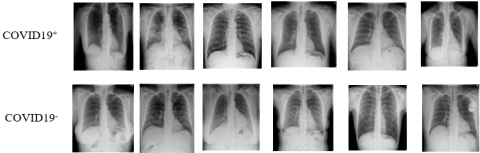

A research team from various countries created this X-ray image dataset in collaboration with doctors in the medical field [30]. The dataset includes 219 X-ray images and 1,341 pictures of normal people. The X-ray images infected are grouped into COVID-19+ and normal COVID-19- pictures are collected. In the Kaggle repository, the X-ray images are collected. The details of the dataset are shown in Table 3, and some of the images are shown in Figure 7.

Figure 7. Sample images of an infected and normal from Dataset 1

Dataset 3

COVIDGR dataset [32] contains total of 852 images. They are categorized into COVID-19+ and COVID-19- cases, 426 positive cases and 426 negative cases. These images were captured using RT-PCR within a time span of at most 24 hours between the x-ray scanned image and the test. The details of the dataset are shown in Table 3, and some of the images are shown in Figure 9.